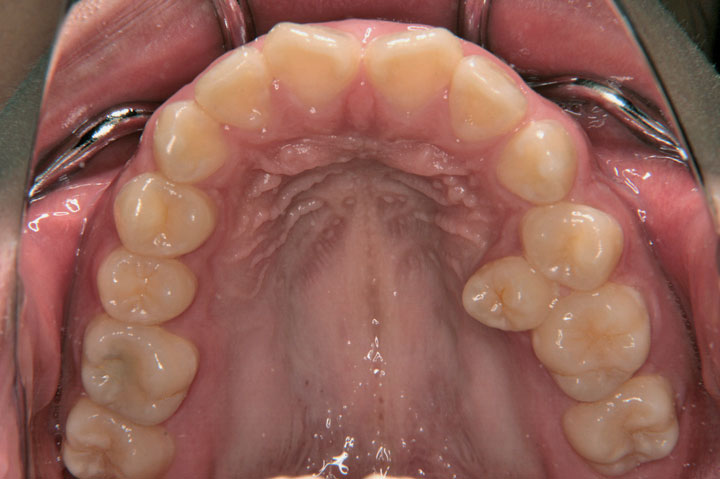

前歯部と上顎左側小臼歯部の不正を主訴に来院された高校1年生の女子です。小臼歯1歯分が歯列からはみ出ており、非抜歯での配列は不可と判断し、上顎両側小臼歯の抜歯ケースとしてエッジワイズ治療を行いました。保定はボンデッドワイヤーとリテーナーを併用しております。

症例画像

初診時

動的治療終了時